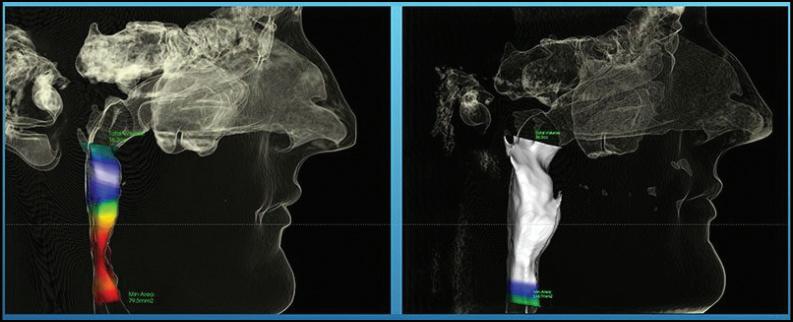

Why TMJ Technology Is So Important

When a patient goes to their TMJ doctor, it is vitally important to make sure that certain technologies are used in order to get a good diagnosis and even greater treatment. In this article we will be looking at the merits of the

dedicated Tesla coil, the x-rays to look at the jaw joints, the digital impression scanner, and the ever so important computer.

When it comes to getting a really great MRI of your TM joints, it is really important to be sure that the imaging center has a Tesla coil dedicated for this kind of work because it

is so sensitive and can allow us to see the articular discs much better than some older technology. In too many cases, the MRI is done with an inferior machine and the reading is simply not that precise. This will often lead to a misdiagnosis and a path of treatment that costs lots of money, time, and frustration.

We Are NOT Your Typical Dental Office

Another piece of technology in getting proper TMJ treatment involves the x-ray equipment. It is important first of all to go with “green” technology, i.e. low dose radiation and three-dimensional imaging. The 3-D imaging comes in really handy when the doctor wants to see what’s going on behind and around the corners of various bones, especially the condyle or jaw bone. This information helps when trying to correlate to the findings of the MRI; do the slipped discs make sense and is that why the jaw bone has shifted in that direction?

Dr. Brown is highly trained in ALF (Advanced Light Force) therapy. He has over 500 hours in ALF therapy training and has lectured around the world teaching ALF techniques with Dr. Nordstrom, the creator of the ALF appliances. The ALF appliances are thin, conservative appliances that can be used on the upper and lower arches. They hide behind the teeth, are removable and are basically invisible when being worn. This innovative treatment approach is used to address neurological, orthodontic and orthopedic issues, and the benefits are vast. Each appliance is unique to the patient and designed by the doctor to achieve specific goals relating to health, beauty and function. No ALF appliance is the same, and treatment is pain-free.

Airway before ALF Treatment;